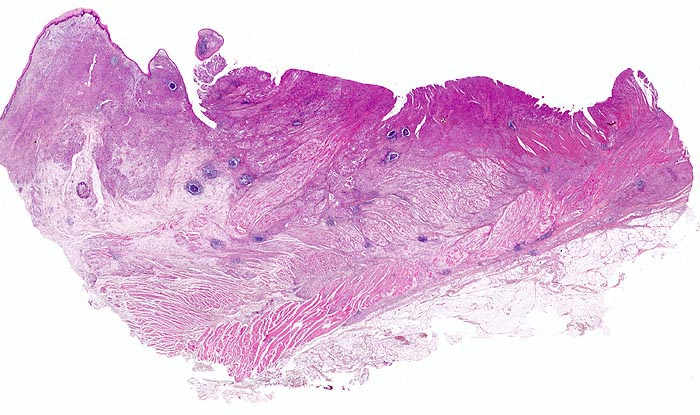

• Gewebsfragment aus gastroösophagealem Übergang.

• Das unscharf begrenzte Karzinom breitet sich diffus in der gesamten Magenwand und in der Ösophaguswand aus bis in des periösophageale und subseröse Fettgewebe.

• Ösophagus mit intaktem plattenepithelialem Schleimhautüberzug.